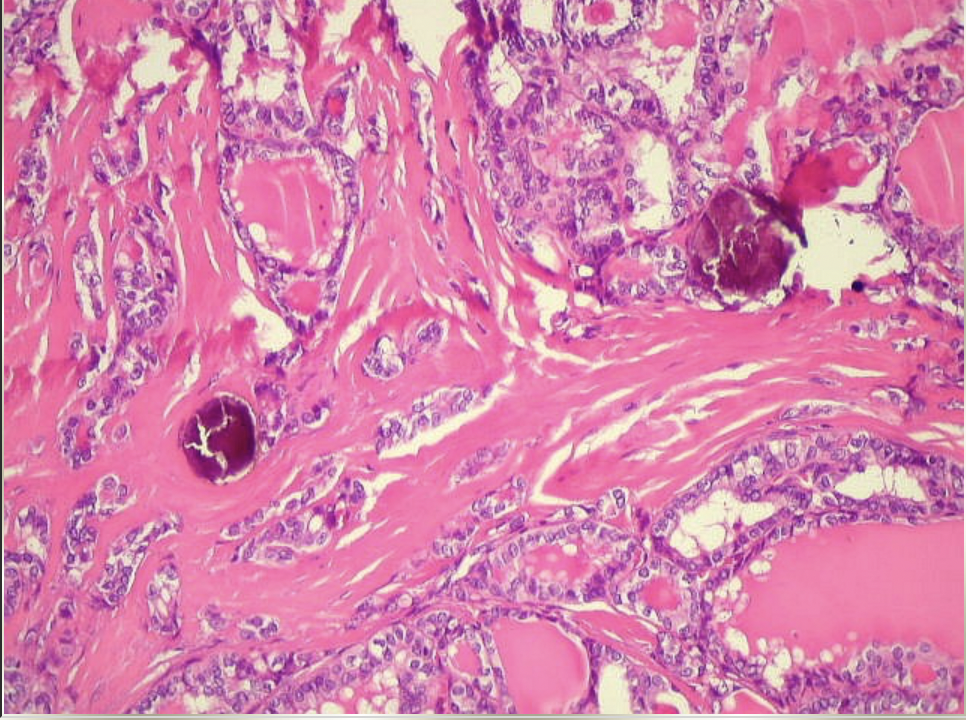

16

Q

Paciente com, 60 anos, com massa anexial em ovário Direito. Realizado anatomopatológico da peça e encontrado o seguinte achado. Qual o achado e possível diagnóstico?

A

Corpo psamatoso - Cistoadenocarcinoma seroso